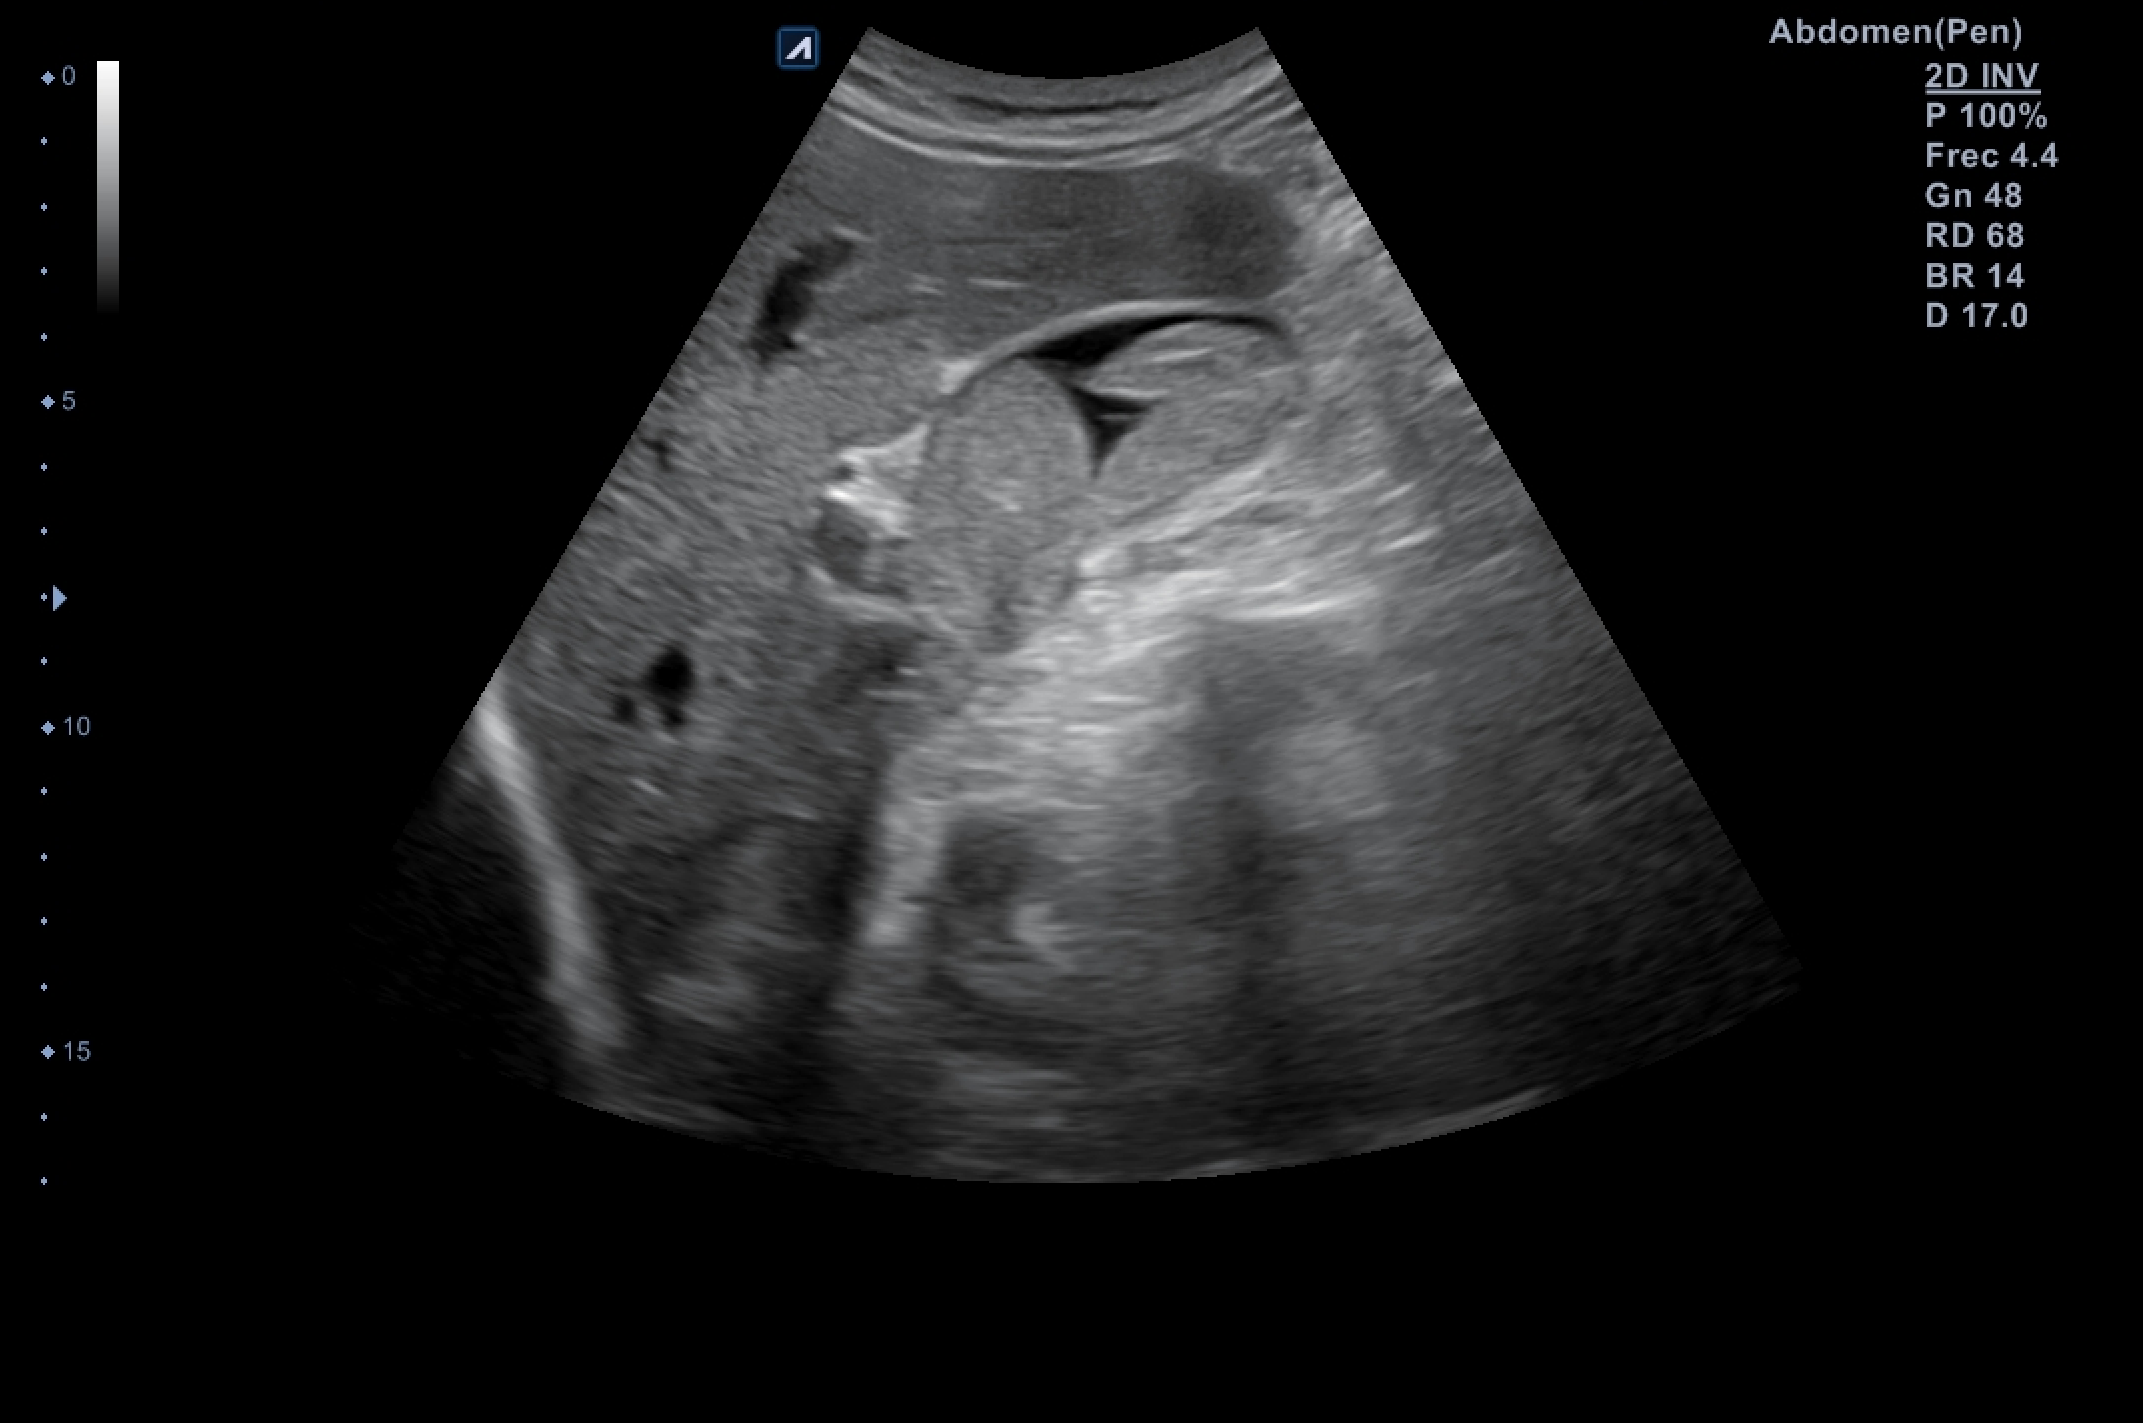

Ecografía abdominal dónde destaca vesícula biliar de pared fina (hasta 3,4 milímetros en su punto de mayor grosor) sin colecciones perivesiculares, que alberga en su interior imagen polilobulada sólida de efecto masa dependiente de su pared posterolateral e inferior que ocupa más de la mitad de la luz, sin captación de flujo Doppler, sugerente de polipoidea o tumoral, de unos 6 x 5 x 3 centímetros de dimensiones mayores.

En muchas ocasiones la ecografía es la prueba oro, ya que es capaz de visualizar lo que otras pruebas, cómo en este caso el TAC, no pueden ver.